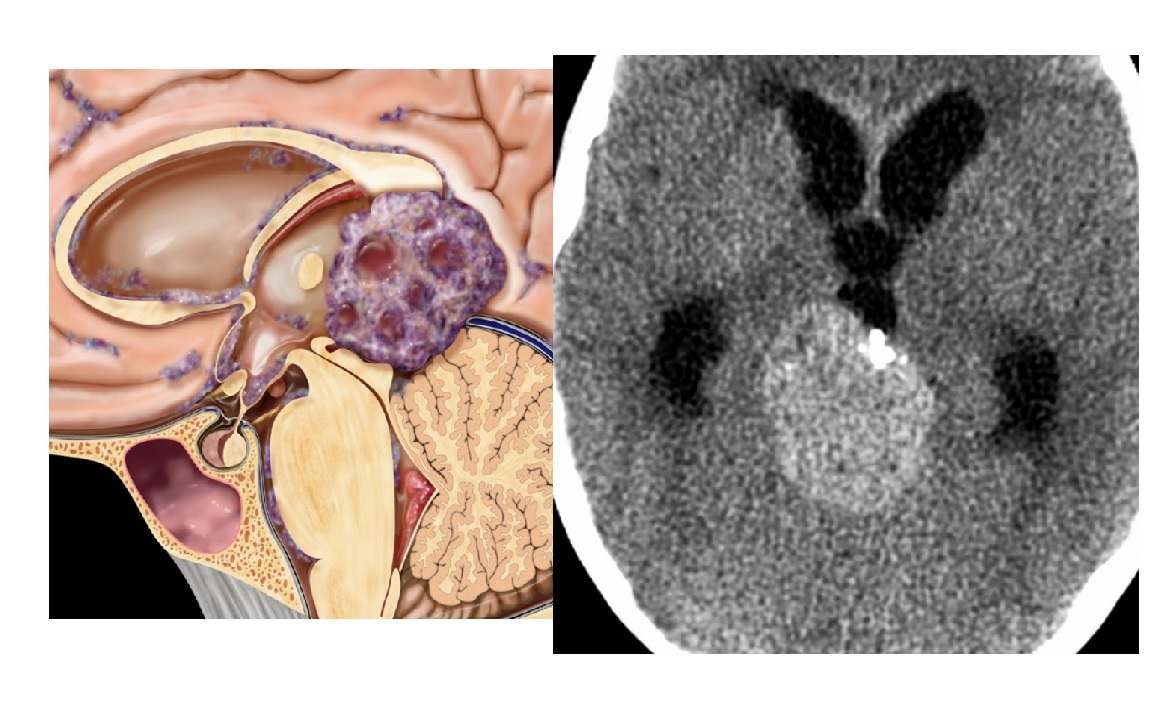

14

Q

Child with large, heterogeneous hyperdense pineal mass with peripheral Ca⁺⁺

A

Pineoblastoma

**Scattered (“exploded”) Ca⁺⁺ rather **than localized (“engulfed”) Ca⁺⁺ in germinoma